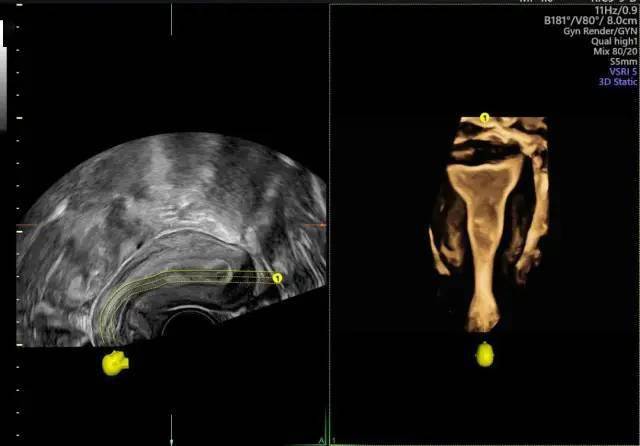

宫腔三维成像(宫腔下段子宫内膜息肉)经阴道四维子宫输卵管造影成像这